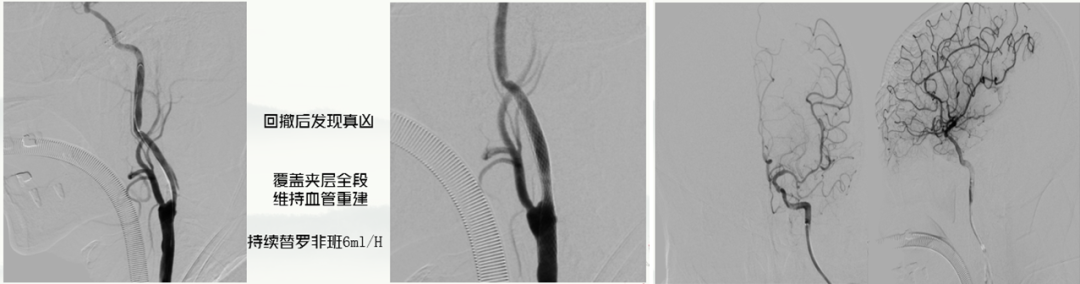

• 导丝回撤时发现“真凶”——颈动脉开口处C1段夹层样改变。

• 选用覆盖率较高的Carotid Wallstent支架覆盖夹层全段,维持血管重建,持续替罗非班6ml/H。

• 左颈总造影显示C1远端逆流,提示串联病变。

• 输送微导丝与中间管,中间管抽吸后在C7段冒烟(A),遂进行微导管造影(B)

• 将中间管送至AB段进行抽吸,中间管只能在M1中段抽吸。

• 抽吸后正位造影显示颅内操作效果良好。

• 输送保护伞,保护伞下撤指引造影侧位C1狭窄。

• 4*30球囊预扩后,将7*40 Carotid Wallstent支架植入后正位,血流得到明显恢复。